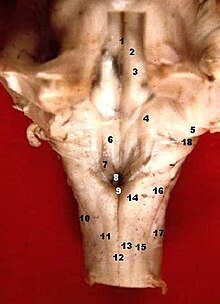

Le centre du vomissement est une structure de la moelle allongée du cerveau qui contrôle le vomissement.

Il est situé dans une zone assez mal limitée située dans le mésencéphale, dans les stries acoustiques de la fosse rhomboïde, à proximité de l'aire vestibulocochléaire. Il mesure environ 1 mm chez l'humain.